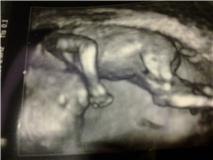

Må jeg præsentere: Abekattebillede!!! Da-daaa!

Faktisk så tynd, at tallet er 1:13.736 ift kromosomfejl! Vi fik en masse flotte 3D billeder - Ingelise var helt vild (I love her).